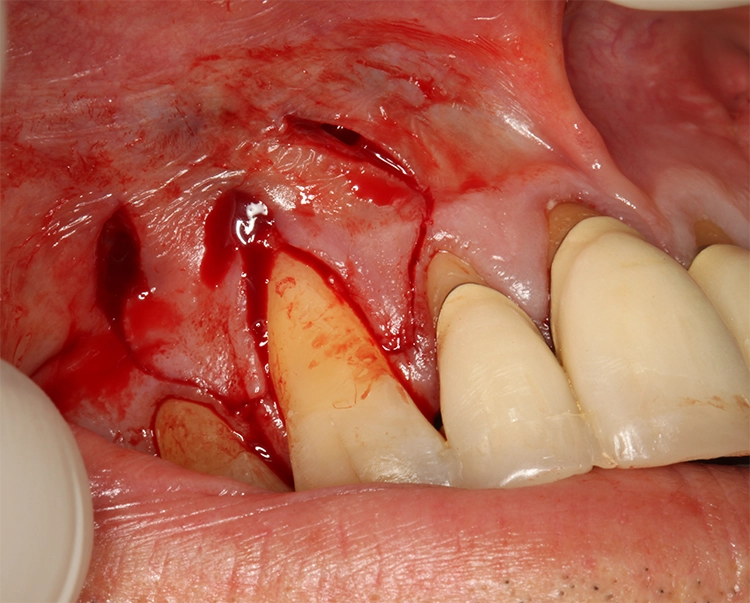

Für die plastische Rezessionsdeckung an den Zähnen 13 und 23 mithilfe von doppelten Papillalappen nach Cohnen und Ross [2], Bindegewebetransplantaten und Schmelz-Matrix-Proteinderivat wurde die Schnittführung mit Split-Flap-Bildung so gewählt, dass möglichst viel keratinisierte Gingiva generiert werden konnte und der Mindestabstand zu den Nachbarparodontien von 1 mm eingehalten wurde (Abb. 13). Ein Gewebekeil wurde apikal der Rezession entfernt und vorerst nur ein Läppchen gesplittet (Abb. 14). Die beiden gesplitteten Läppchen wurden vernäht, wobei ein Mukosaläppchen noch unmobilisiert blieb, um das Aneinandernähen zu erleichtern. Das Vernähen erfolgte von koronal nach apikal, danach wurde das zweite Läppchen vollständig mobilisiert (Abb. 15).

Egger/Wermuth/Greven